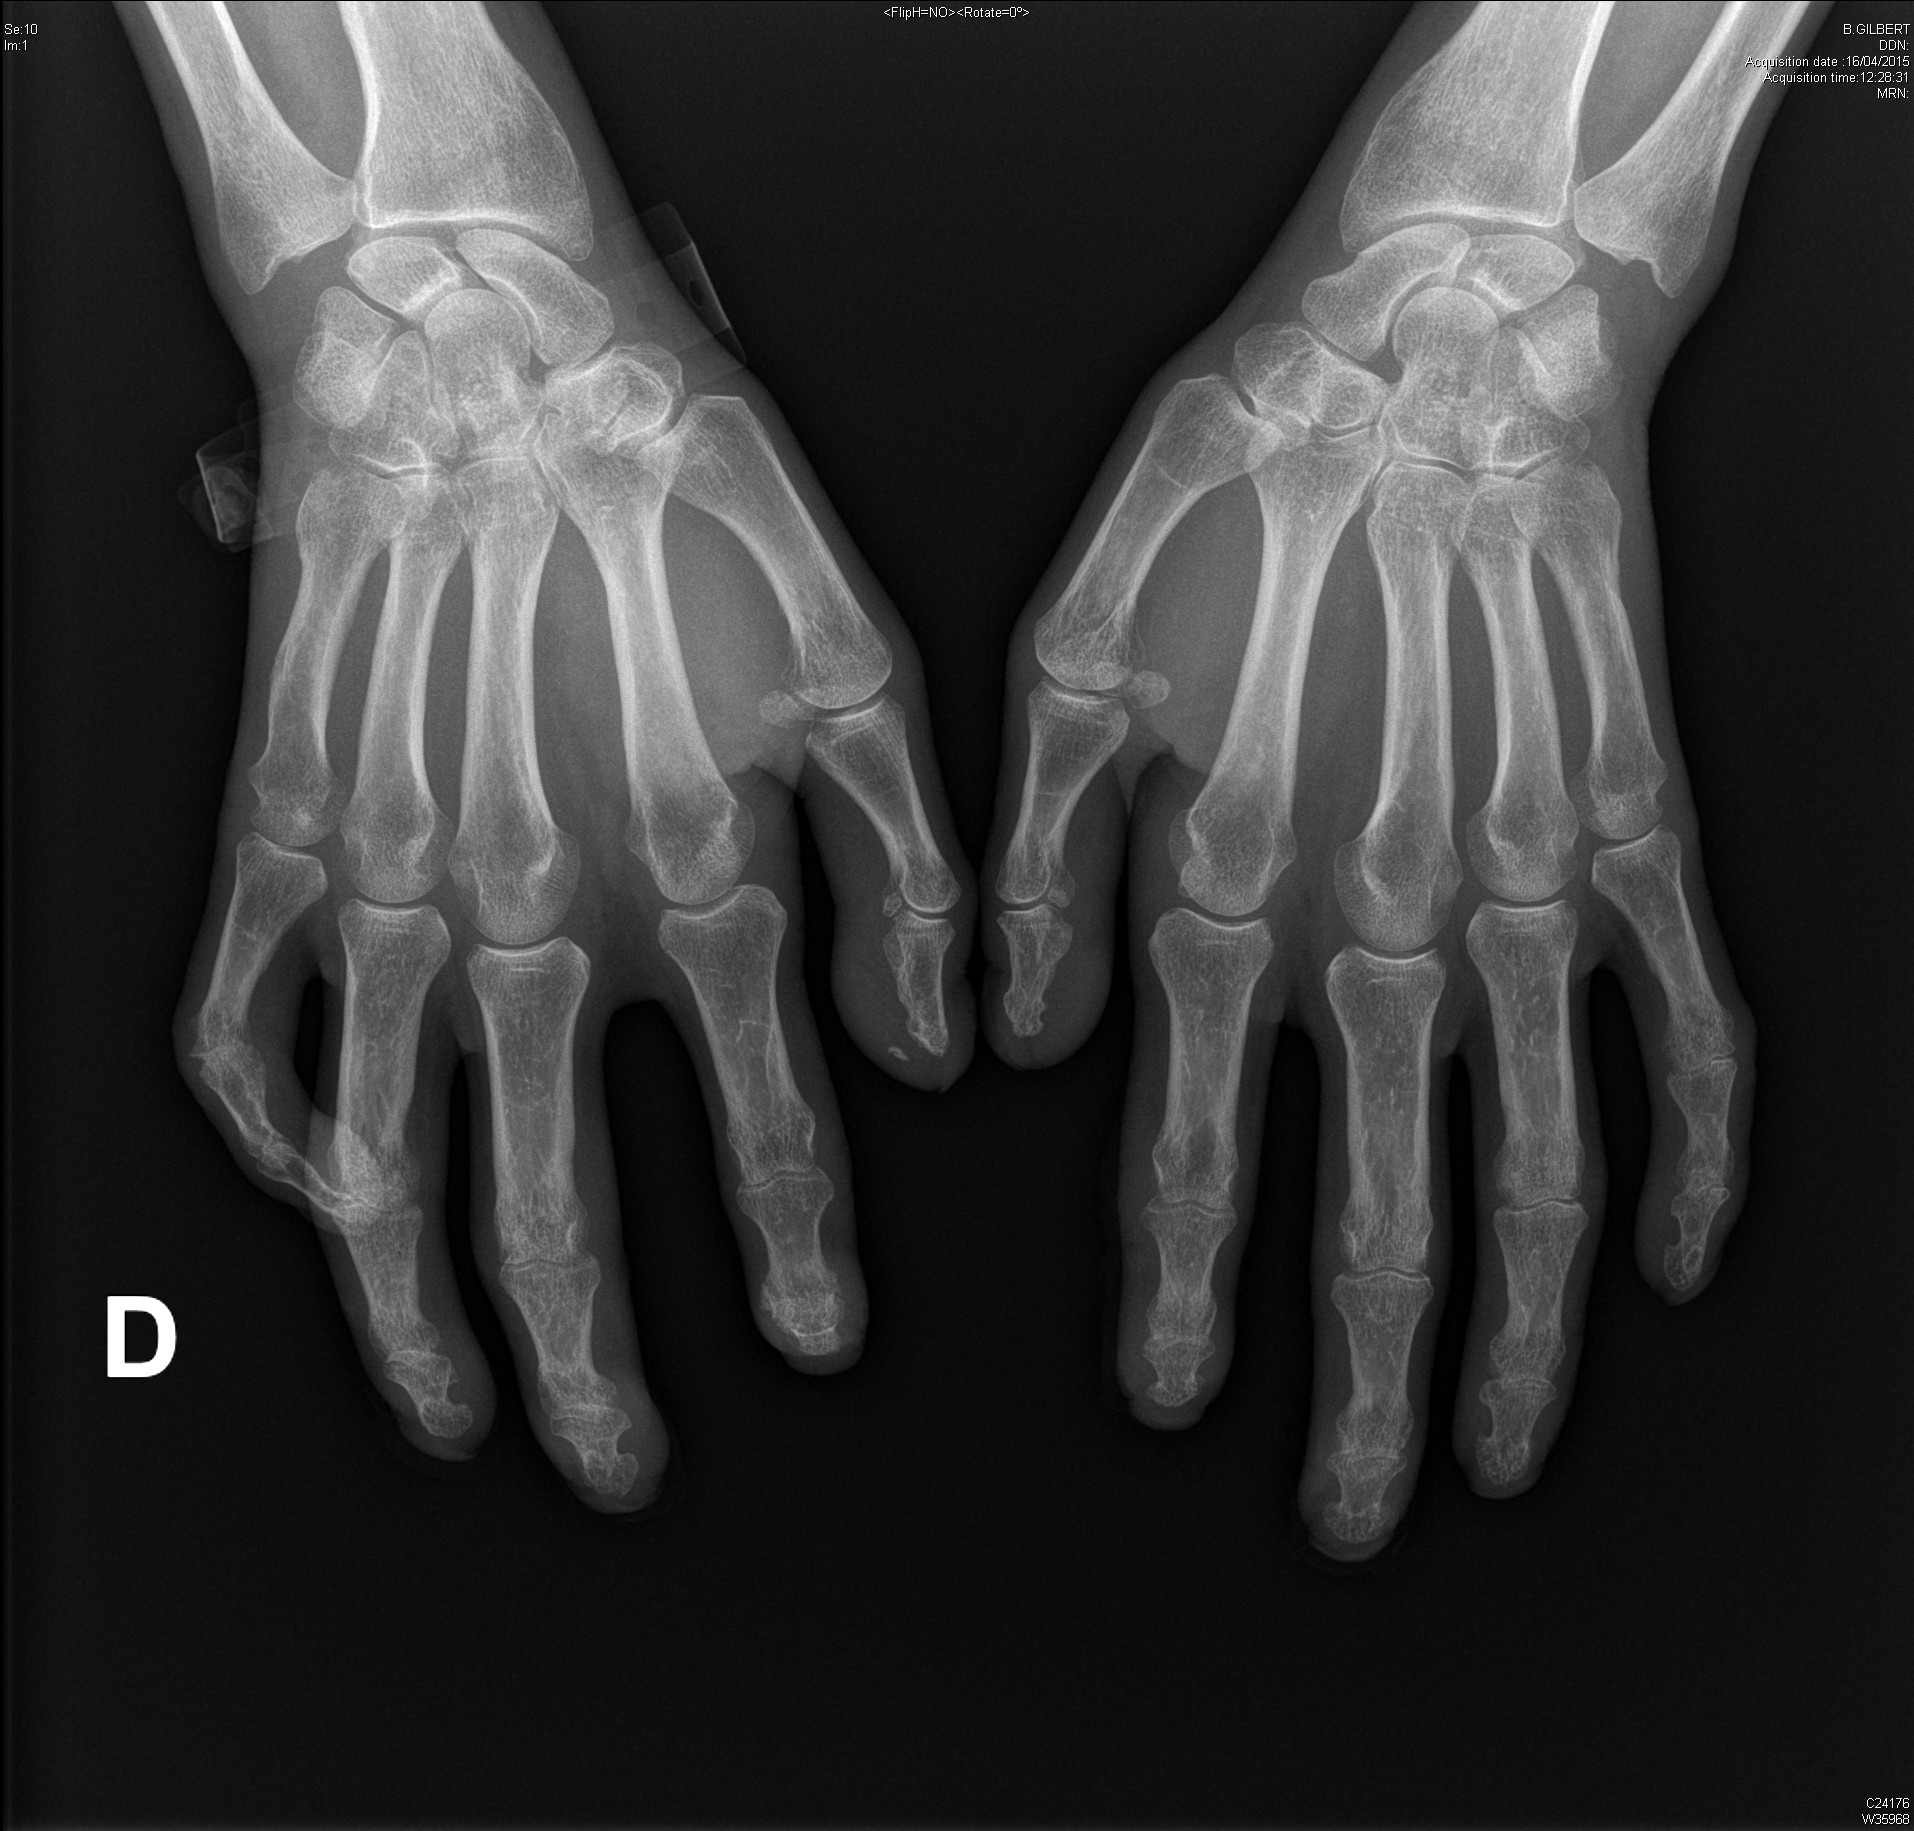

Polyarthrite rhumatoïde débutante, d'emblée érosive

polyarthrite rhumatoïde érosive avec signe de Freiberg radiographique au poignet